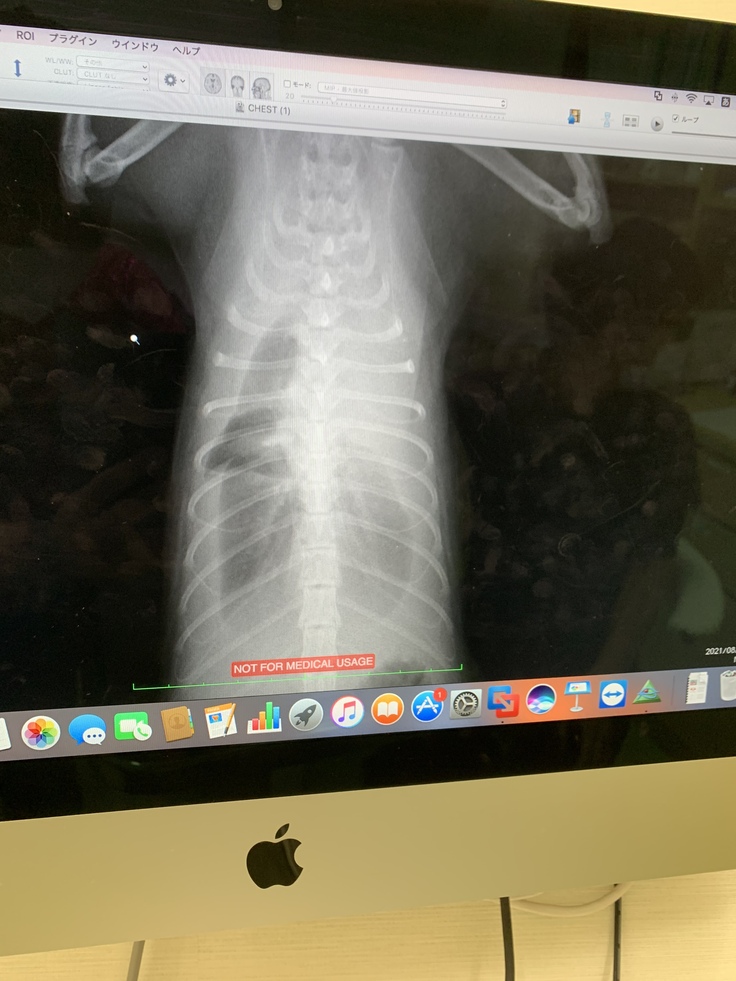

【8月5日】

このめの呼吸がおかしい事に気付き、行きつけの動物病院を受診しました。

検査の結果、胸水が溜まっていて早急に対応しないと命に関わると…。

水が溜まった原因は、検査をしないとわからないが、膿胸かFIPと言われました。

急遽その日から入院となり、酸素室で点滴されているこのめと別れました。

白く見えるのが水です。